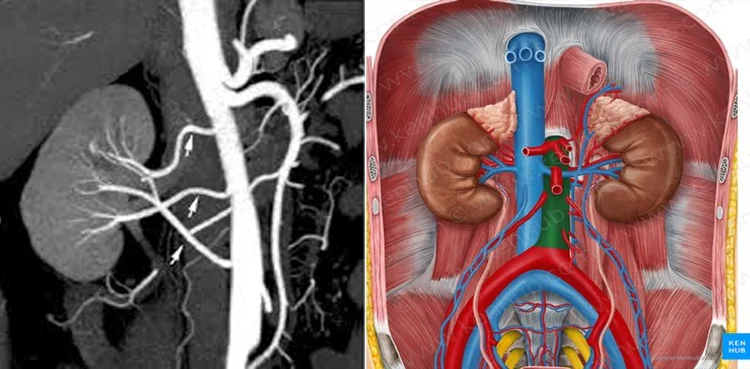

اسلام آباد(روشن پاکستان نیوز) رینل آرٹری سٹیناسس ایک ایسی سنگین طبی حالت ہے جس میں گردوں کو خون پہنچانے والی شریانیں سکڑ یا تنگ ہو جاتی ہیں۔

گردوں کی شریانیں تنگ ہونے کے نتیجے میں گردوں تک آکسیجن اور غذائیت سے بھرپور خون مناسب مقدار میں نہیں پہنچ پاتا، جس سے ان کی کارکردگی متاثر ہونے لگتی ہے۔

گردوں کی کارکردگی کیوں متاثر ہوتی ہے؟

گردے ہر منٹ بڑی مقدار میں خون فلٹر کرتے ہیں اور جسم کے فضلات کو پیشاب کے ذریعے خارج کرتے ہیں۔ جب گردوں کی شریانیں تنگ ہو جائیں تو خون کا بہاؤ کم ہو جاتا ہے، جس کے باعث گردے صحیح انداز میں فلٹریشن نہیں کر پاتے۔ اس سے نہ صرف جسم میں زہریلے مادے جمع ہونے لگتے ہیں بلکہ بلڈ پریشر بھی بڑھ جاتا ہے، اور وقت کے ساتھ گردے ناکارہ ہونے کا خطرہ پیدا ہو سکتا ہے۔

رینل آرٹری سٹیناسس کی سب سے عام وجہ شریانوں میں چربی، کولیسٹرول اور دیگر مادوں کا جمع ہونا ہے، جسے ایتھروسکلروسیس کہا جاتا ہے۔ یہ تہیں شریانوں کی دیواروں کو سخت اور تنگ کر دیتی ہیں۔

دوسری اہم وجہ فائبرومسکلر ڈیسپلاسیا ہے، جس میں شریانوں کی دیواروں کے خلیات غیر معمولی انداز میں بڑھتے ہیں۔ یہ کیفیت زیادہ تر پیدائشی سمجھی جاتی ہے اور نوجوان افراد میں بھی دیکھی جا سکتی ہے۔